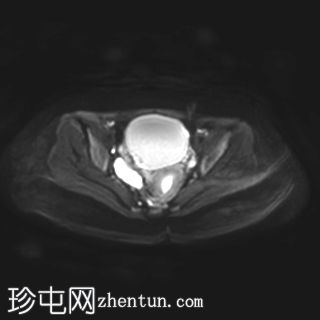

轴位

T2加权像

右侧卵巢增大,卵泡呈周边排列。

附件血管蒂扭转(漩涡征)。

右侧附件旁可见一较大的、边界清晰的盆腔囊性病变,向右倾斜,提示为卵巢旁囊肿。

本病例展示了卵巢扭转的典型影像学特征,包括卵巢增大、卵泡呈周边移位、卵巢向内侧偏移以及特征性的漩涡征。

在这种情况下,较大的卵巢旁囊肿被认为是发生卵巢扭转的高危因素。如果卵巢旁囊肿较大(>5厘米)或活动度较大,其重量/活动度增加会牵拉附件,导致卵巢和输卵管发生扭转。